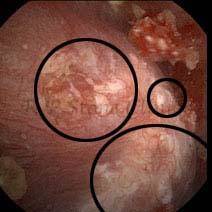

Kidney stone is a solid mass of CRYSTALS. It is the process of crystallization which initiates the formation of kidney stones. This happens in nephrons or units of kidney. Once a small crystal is formed, it can both grow & unite with other crystals leading to the formation of small concretion which eventually forms a stone. Once these large crystals detach from the collecting ducts, the process of stone formation starts in the renal collecting system. A recurrent kidney stone former is advised to know a little bit about something known as Randall’s plaque. Alexander Randall discovered plaques on the renal papillae eight decades back based on examination of 1154 pairs of autopsied Kidneys. He described these renal papillary lesions as cream colored or milk patch areas composed of calcium phosphate & calcium carbonate. These plaques could act as NIDUS for formation of KIDNEY STONE. Calcium Oxalate stone can form on this nidus & then detaches from this plaque to become a free floating stone in the collecting system of kidney

These images are taken as snap shots from the video recording of RIRS Surgery done at our hospital. These are Randall’s Plaques seen with Digital FLEX XC & Digital FLEX XC S. The cream or whitish patches are seen on the tips of RENAL PAPILLAE as seen in images below.

Randall’s Plaques may lead to the formation of Stones.

Those kidney stone patients who have Randall’s Plaques in their kidneys are more likely to form stones again (Recurrent Stones).

Stone Patients in whom Randall’s Plaques are detected at the time of RIRS Surgery should undergo regular ultrasound examination for early detection of stones.

Patients of Stones with Randall’s Plaques in their Kidneys should drink plenty of fluids in addition to Orange Juice & Lemonade.